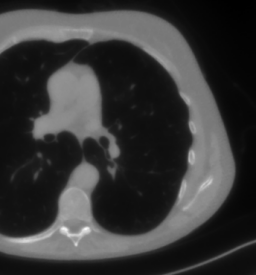

As real patient images, we have downloaded the widely used AAPM Low Dose CT Grand Challenge data set by the Mayo Clinic [35]. The considered images are 512×512512512512\times 512 pixel reconstructions of human abdomen, computed from full-dose acquisitions. In Figure 2 we depict one image with two zooms-in highlighting areas with different anatomical structures, such as pulmonary details, sections of ribs and low-contrast inter-costal muscles. In all the experiments reported in 5.1, we have used the images from the data set as ground truth xGTsubscript𝑥𝐺𝑇x_{GT} references. Coherently, we simulate the tomographic projections of the ground truth images, according to a 2D fan-beam geometry, and we add to the sinograms white Gaussian noise with 102superscript10210^{-2} noise level. To address sparse-view CT reconstructions, we considered two different protocols: the first one is a full angular acquisition with 1-degree spaced projections (we call it P360,360subscript𝑃360360P_{360,360} in the following); in the second one the scanning trajectory covers 180180180 degrees and computed only 606060 projections (it is labelled as P180,60subscript𝑃18060P_{180,60}).

Refer to caption

Figure 2: A ground-truth image from the Low Dose Mayo data set, with two zoomed crops on regions with different anatomical structures.